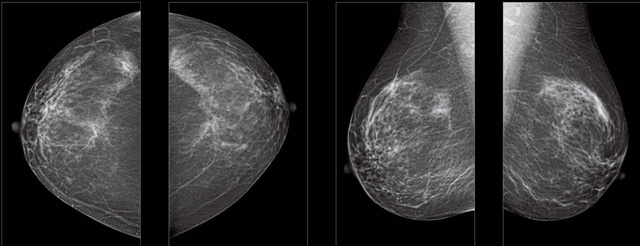

首先不同年齡階段的乳腺篩查頻次種類不一樣。青春期女性第二性征明顯發(fā)育開始,每個(gè)月進(jìn)行自我乳腺檢查。20-30歲的女性就不推薦進(jìn)行乳腺檢查,因?yàn)槟贻p女性的乳腺組織非常緊急。鉬靶X光線等檢查的射線不能辨別腫塊跟腺體。身體就白吸收了輻射,影響了身體健康。每個(gè)月自檢一次就是在洗澡時(shí)候,對著鏡子看看乳房外觀正常,皮膚潰爛、腫塊、顏色改變、再摸一下有沒小疙瘩。乳腺高危人群,特別是有乳腺CA遺傳傾向的女性,乳腺導(dǎo)管跟小葉不典型增生,原位癌。30歲前有乳房放療的女性。乳腺癌篩查可以把年齡提前到40歲前。40到70歲的女性可以在適合的機(jī)會篩查。

采用影像檢查技術(shù)來發(fā)現(xiàn)疑似特定病檢查跟人群的普查。一到兩年進(jìn)行一次X光線的乳腺檢查。記過是C或者D型,可以加上B超協(xié)同。還可以一年一次核磁共振MRI檢查。70歲以上的女性認(rèn)為絕經(jīng)的女性是比較安全的。實(shí)際上也有乳腺癌的風(fēng)險(xiǎn)。65歲以上風(fēng)險(xiǎn)也很大。也是需要進(jìn)行機(jī)會性篩查。